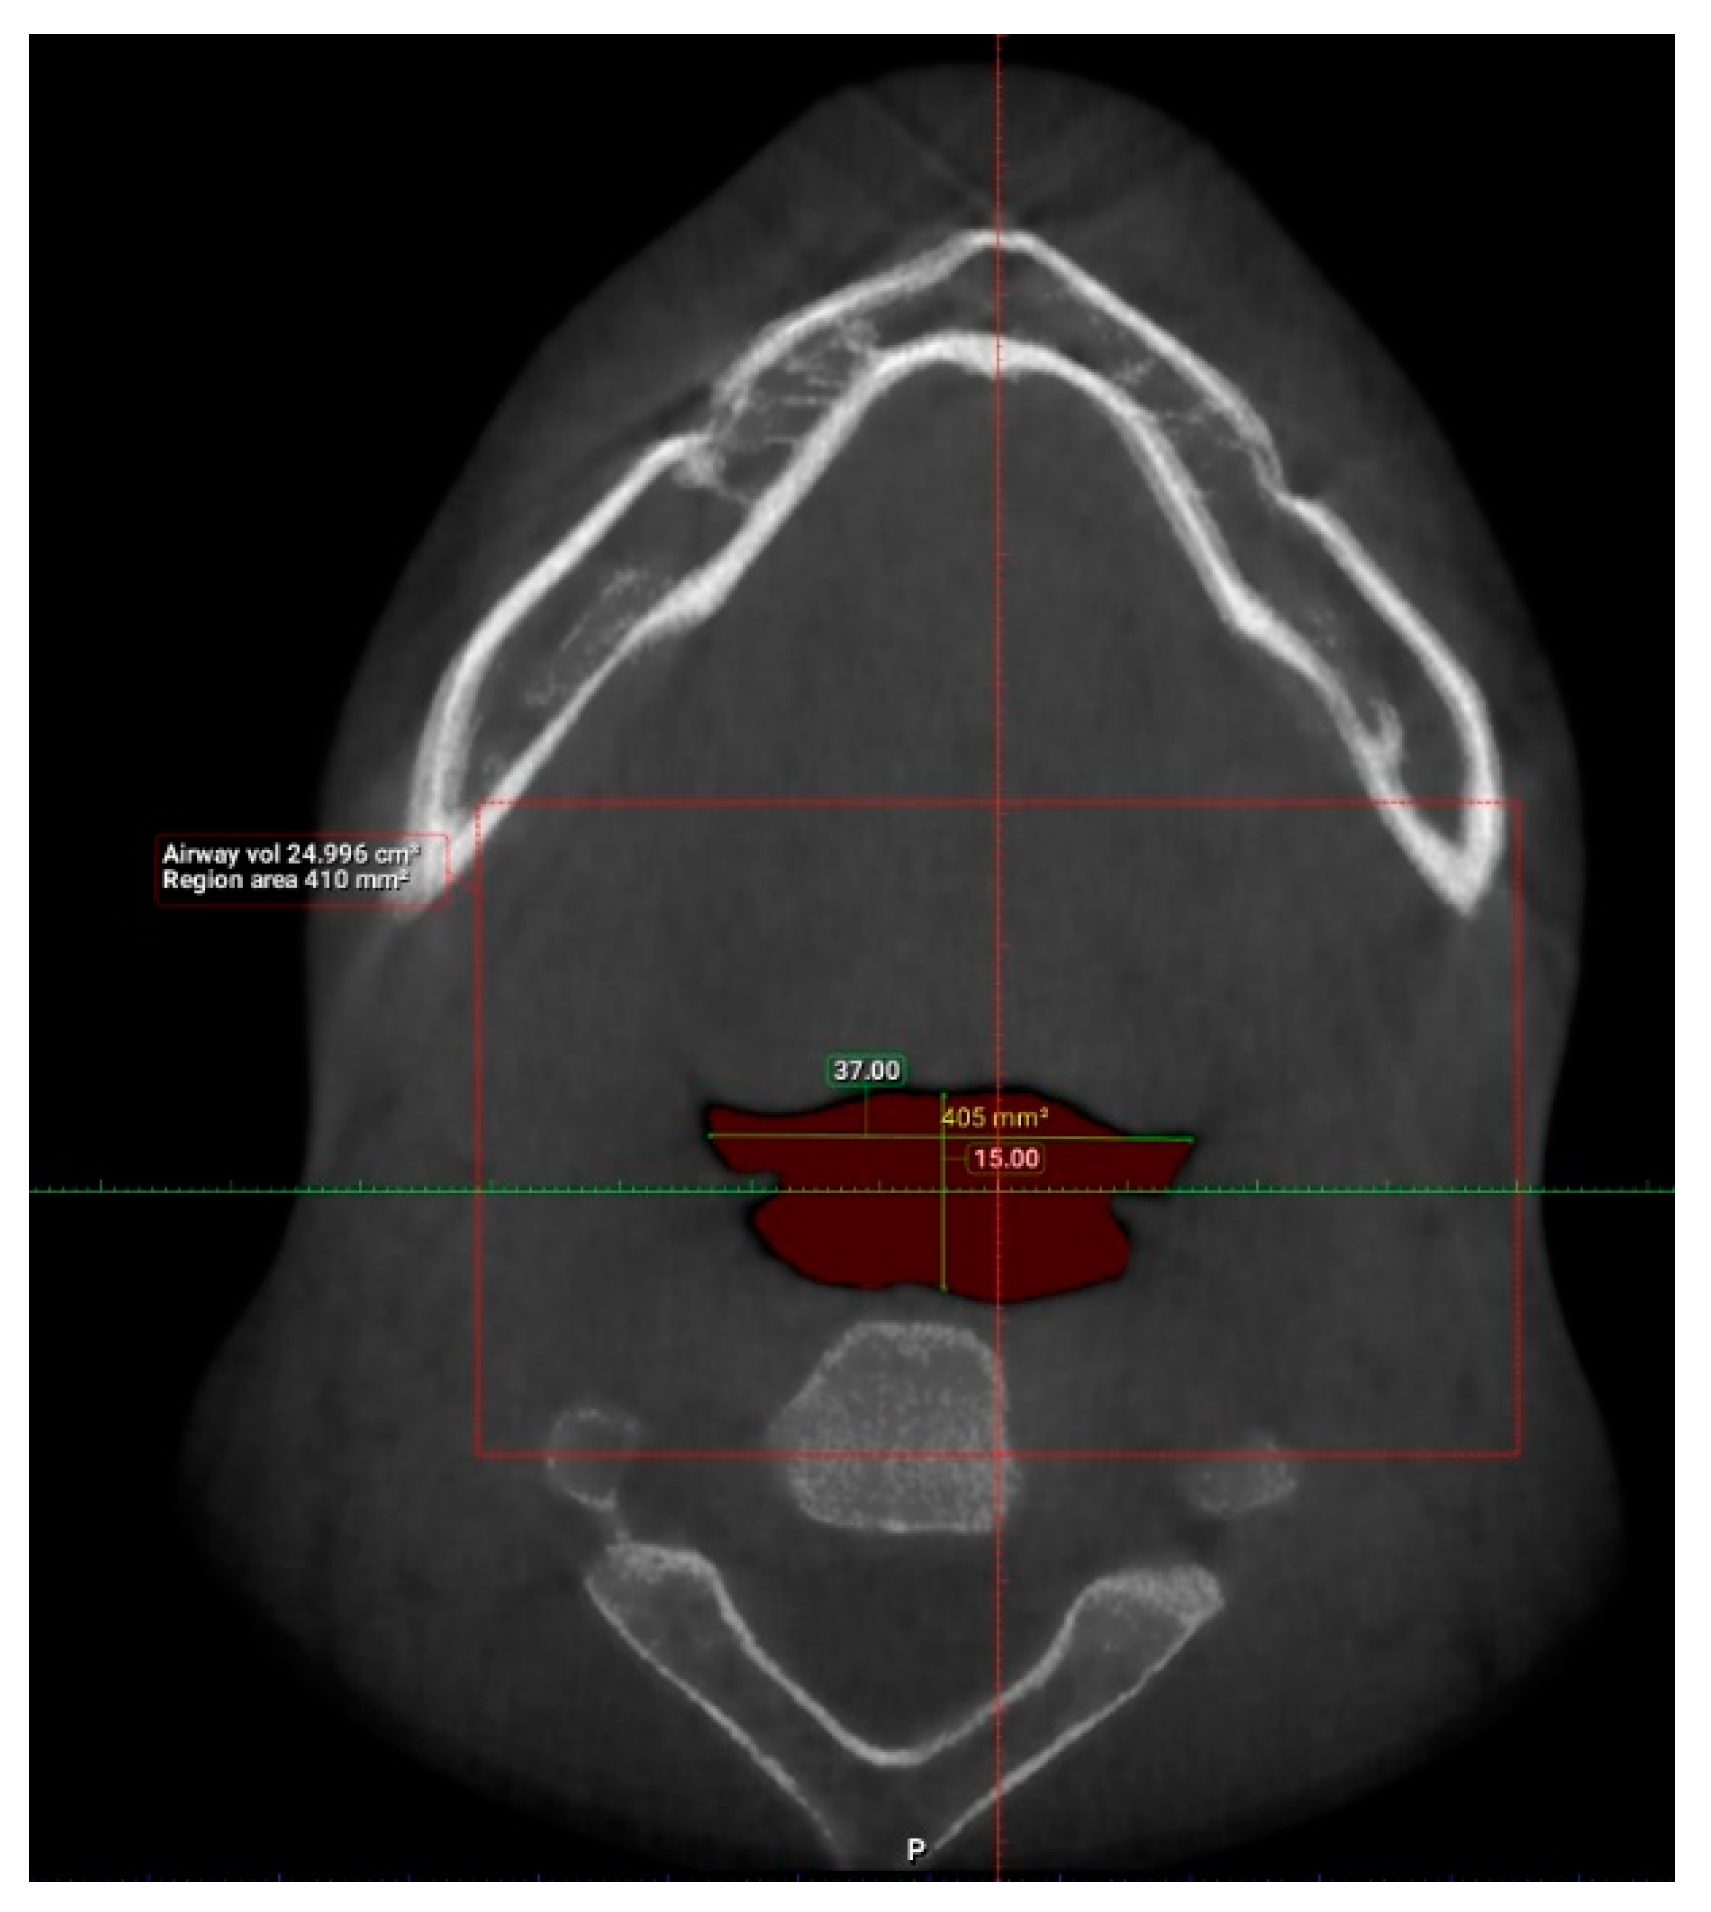

| N | Minimum | Maximum | Mean | Std. Deviation | |

| Length (mm) | 101 | 29.93 | 55.75 | 42.63 | 6.24 |

| Total volume (cm3) | 101 | 94.58 | 173.45 | 131.67 | 17.91 |

| Average volume (cm3) | 101 | 3.34 | 32.09 | 11.10 | 5.21 |

| Antero-posterior (mm) | 101 | 1.00 | 14.50 | 6.44 | 3.19 |

| Width (mm) | 101 | 8.00 | 37.00 | 21.69 | 6.54 |

| Valid N (listwise) | 101 |